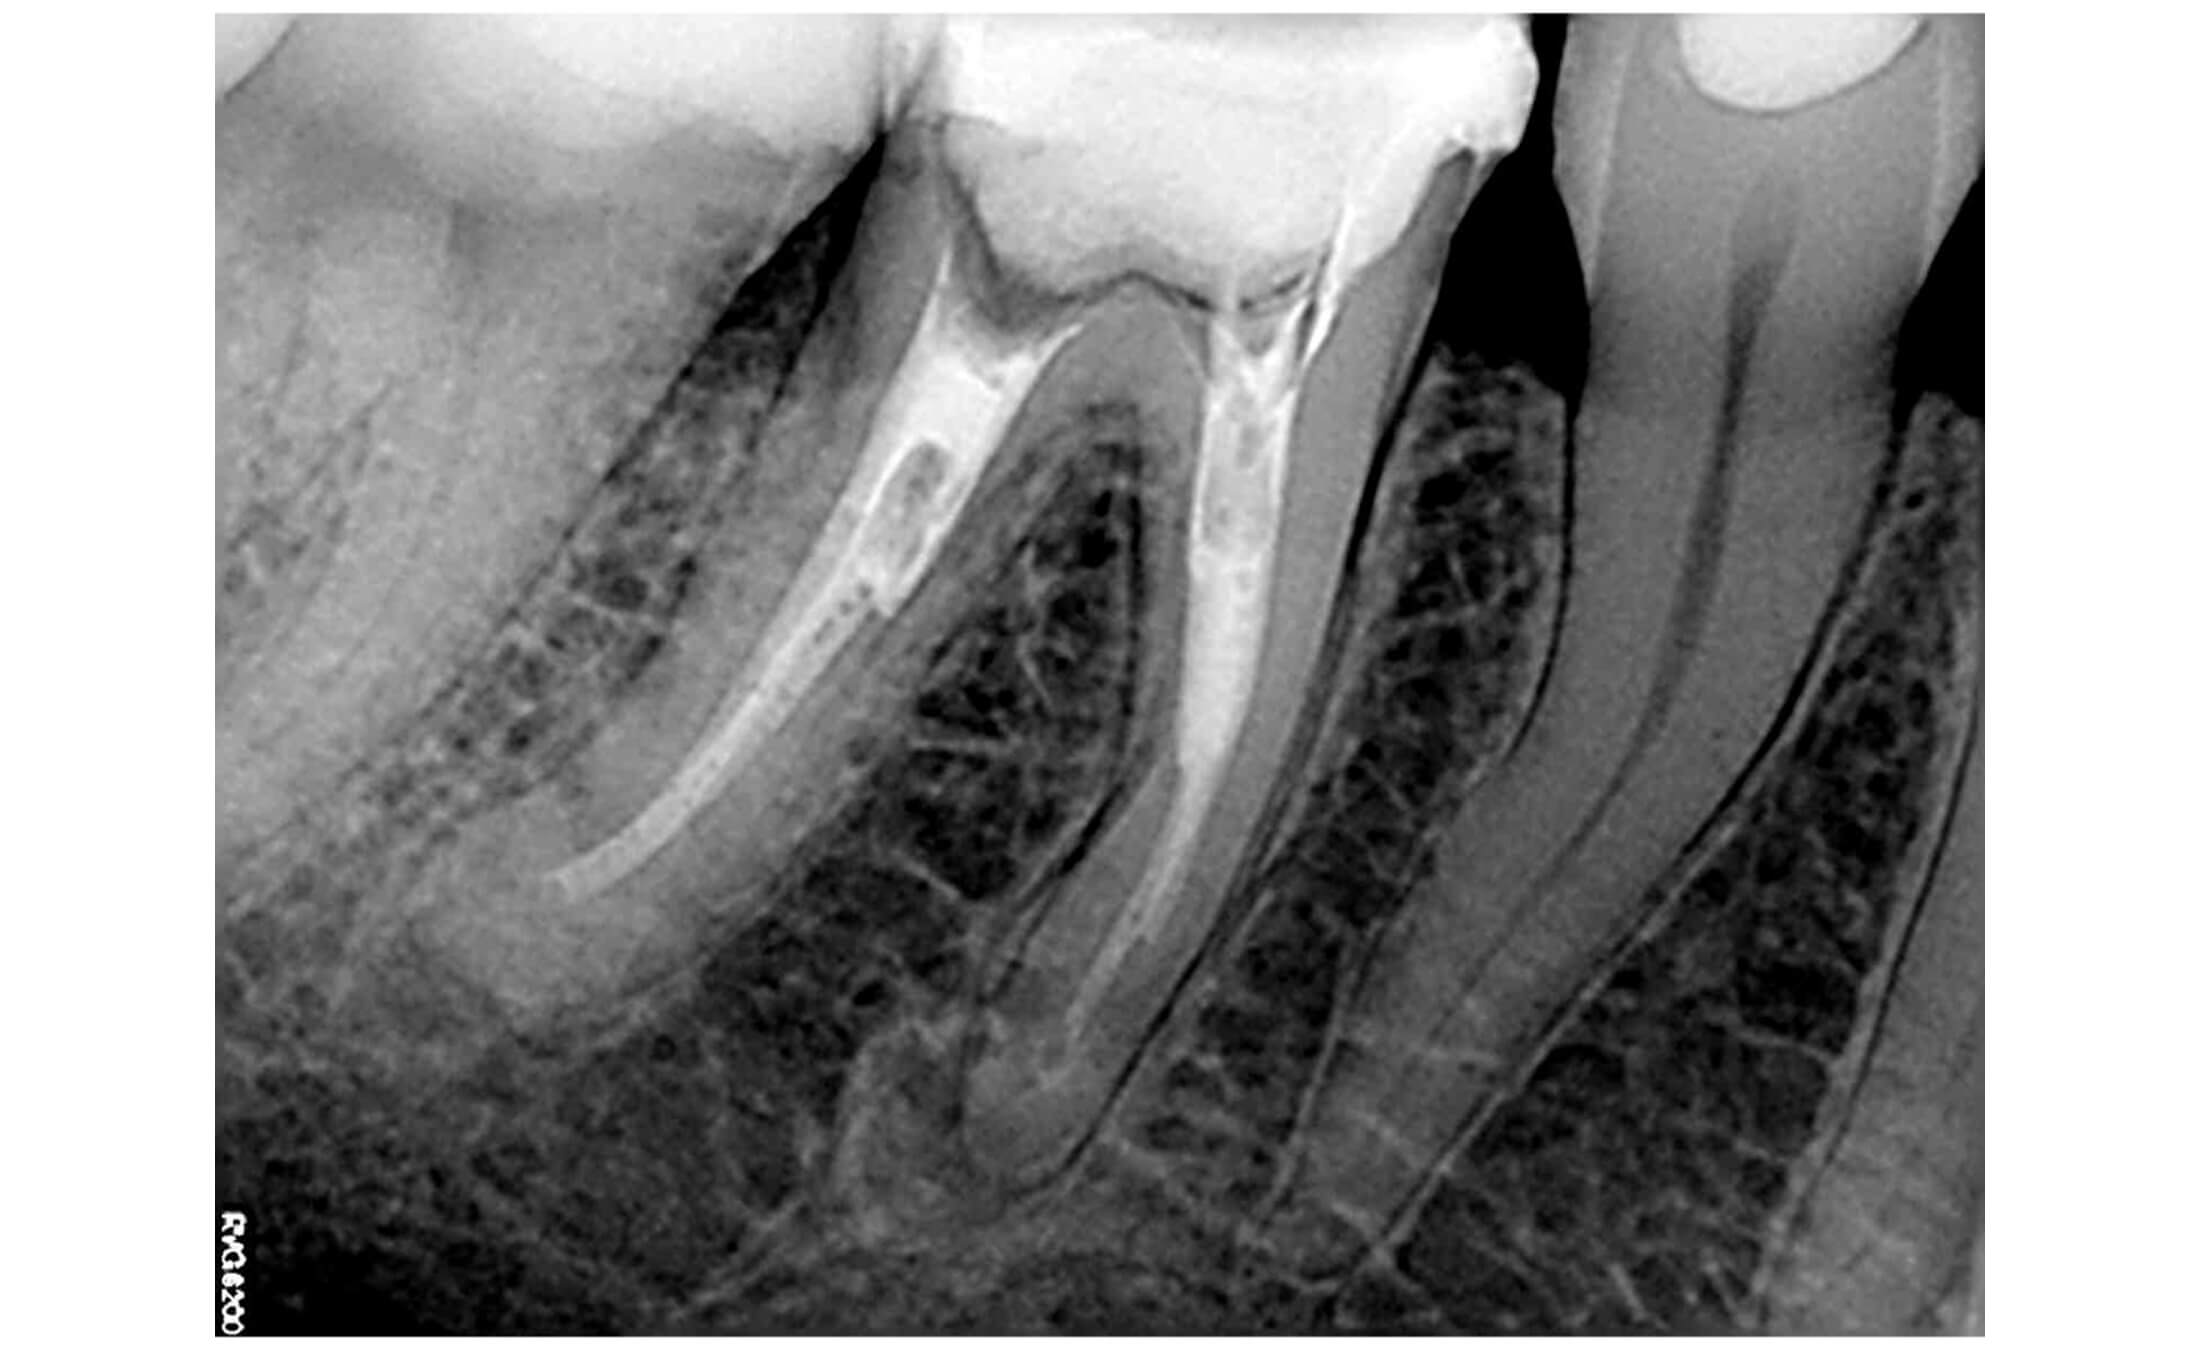

1. Исходная ситуация, зуб 46, апикальный периодонтит, в каналах мезиального корня сломаны два эндодонтических инструмента, устья перерасширены, в дистальном корне - два стекловолоконных штифта установленных в ступень не по оси канала. (Фото 1,2,3)